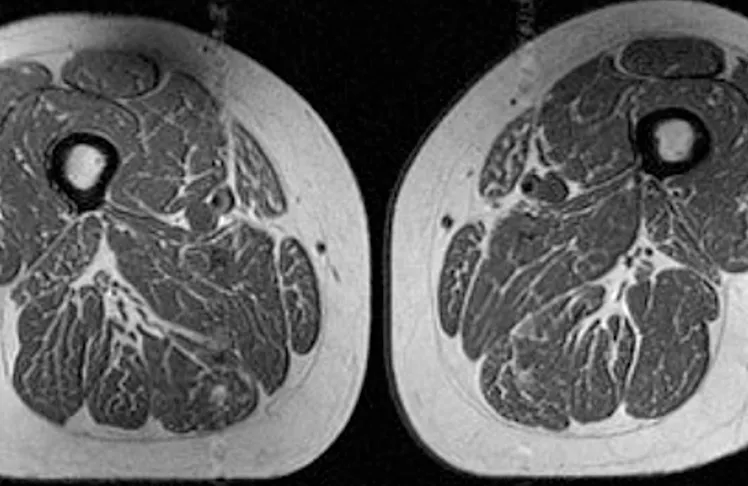

(CNN) — The image looks like a slice of highly marbled flesh, reminiscent of a high-end steak with abundant fine-grained streaks of fat. But that’s not dinner. It’s an MRI scan of the thigh of a 62-year-old woman who obtained 87% of her annual calories from ultraprocessed food.

A 61-year-old woman in the study also had fat marbling in her thigh muscles, but it was not as intense. About 29% of her annual diet consisted of ultraprocessed foods.

The 61-year-old woman with a diet consisting of 29.5% ultraprocessed food (A in image below) had a slightly higher BMI of 32.6 and a much lower activity score than the woman (B in image) with a BMI of 31.8 whose diet was 87.1% ultraprocessed. Yet the woman with the higher ultraprocessed score still had dramatically more fat marbling in her thighs.